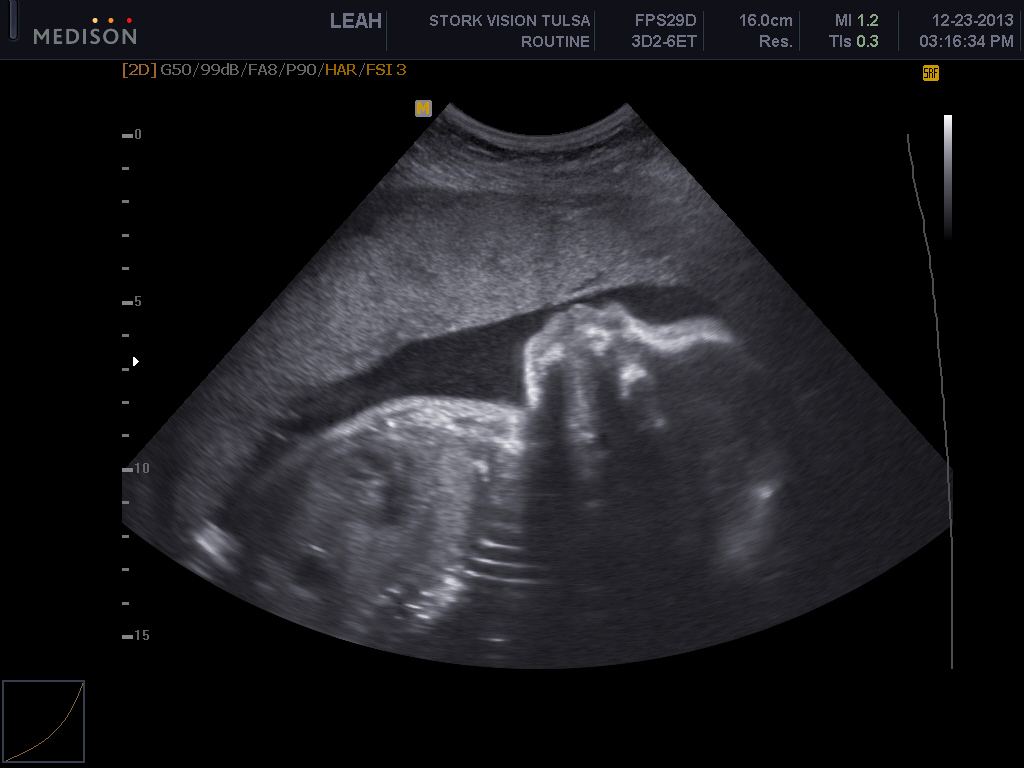

These ones below show him stretching and its just so cute to me!!